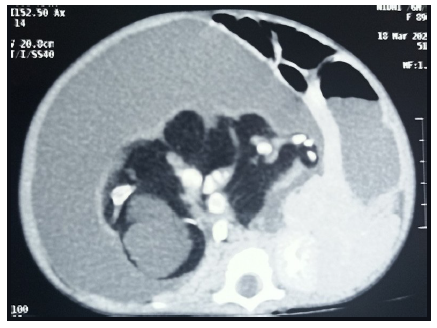

A 5-month-old female infant presented with gross abdominal distension associated with respiratory distress. The parents reported the presence of an abdominal mass since birth, which had gradually progressed. The child was born at full term via caesarean section without any complications. There was no history of twin birth in the family. On examination, the child exhibited hurried breathing with distress and marked abdominal distension. A firm, non-tender, well-defined spherical mass was palpable, occupying the upper and lower quadrants of the right side of the abdomen and extending across the midline. Routine blood investigations were within normal limits. Serum alpha-feto protein (AFP) levels were elevated, while serum beta-human chorionic gonadotropin (HCG), carcinoembryonic antibody (CEA) levels were within normal range. Abdominal ultrasonography revealed a large cystic mass with internal solid components resembling limb buds in the right retroperitoneal region. The bowel loops were found to be pushed anteriorly. Contrast-enhanced computed tomography (CECT) of the abdomen revealed a well-encapsulated, multi-loculated solid-cystic lesion containing intralesional fat components and calcifications forming appendiceal bones in the right retroperitoneum (Figure 1). Based on the presence of limb buds and appendiceal bones, fetus in fetu was considered the most likely diagnosis, with a highly organized teratoma kept as a differential.